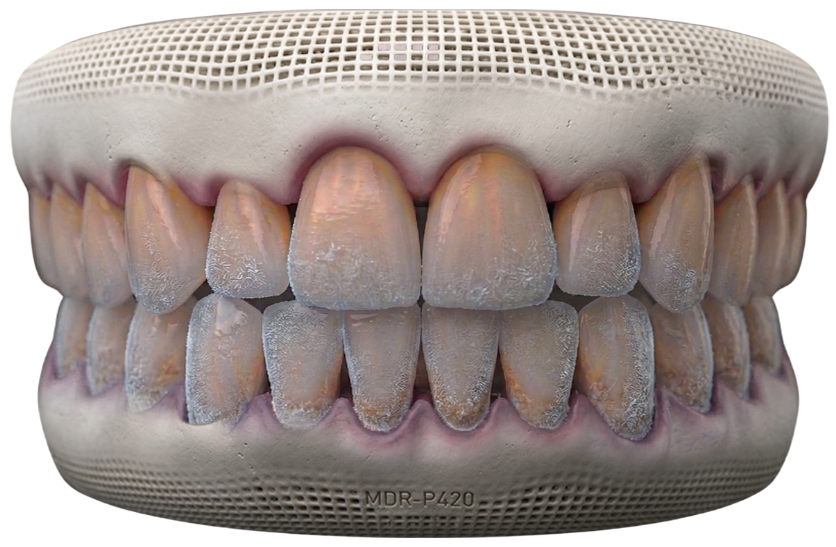

Microscopic Root Canal

Enhanced Precision & Accuracy

Magnification allows us to locate and treat even the most complex or hidden canals with exceptional detail and control.

Minimally Invasive Approach

Preserves more of your natural tooth structure while effectively removing infection and preventing further damage.

Your Microscopic Root Canal Journey

Precision Cleaning & Shaping

Infected pulp is carefully removed, and the canals are cleaned and shaped under microscopic guidance.

Sealing & Protection

The canals are sealed to prevent reinfection, and the tooth is prepared for final restoration if needed.